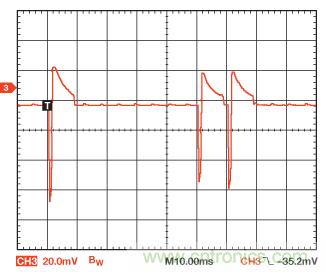

圖7所示為心臟再同步器件起搏模式在鹽水箱中的示波器軌跡。這是起搏器驗(yàn)證的標(biāo)準(zhǔn)測試環(huán)境;大家認(rèn)為,鹽水的導(dǎo)電性能與人體相似。由于示波器探頭十分接近起搏導(dǎo)聯(lián)線,結(jié)果導(dǎo)致幅度遠(yuǎn)遠(yuǎn)大于皮膚表面的預(yù)期值。另外,由于鹽溶液導(dǎo)致心電圖電極阻抗變低,結(jié)果使噪聲遠(yuǎn)遠(yuǎn)低于皮膚表面測量的正常值。

圖7. 再同步器件在鹽水箱捕獲的起搏信號

第一個(gè)脈沖是心房,第二個(gè)脈沖是右心室,第三個(gè)脈沖是左心室。導(dǎo)聯(lián)線置于鹽水箱中,其矢量經(jīng)過優(yōu)化以便把脈沖清晰地顯示出來。負(fù)向脈沖為起搏,正向脈沖為再充電。心房脈沖的幅度略大于其他兩個(gè)脈沖的幅度,因?yàn)閷?dǎo)聯(lián)線的矢量稍微好于兩根心室導(dǎo)聯(lián)線,但在實(shí)際應(yīng)用中,再同步器件中的全部三個(gè)起搏輸出都編程為相同的幅度和寬度。對于真正的患者,每根起搏器導(dǎo)聯(lián)線的幅度和寬度一般都是不同的。